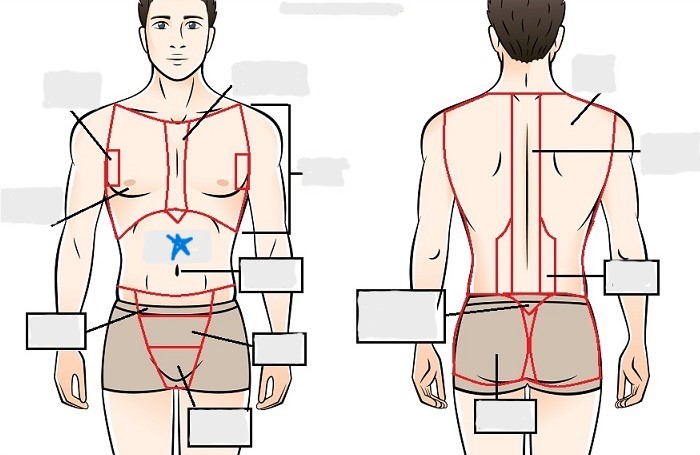

axial

cephalic

occipital

frontal

otic

orbital

nasal

oral

mental

cervical

dorsal

scapular

vertebral

lumbar

sacral

gluteal

thoracic

sternal

mammary

axillary

abdominal

umbilical

pelvic

inguinal

pubic

perineal

appendicular

acromial

brachial

antecubital

olecranal

antebrachial

carpal

manus

coxal

femoral

patellar

popliteal

crural

sural

peroneal

calcaneal

plantar